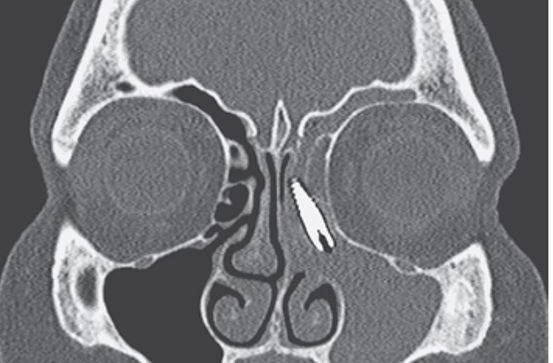

10、乱跑的螺丝

一名57岁女性患者因鼻窦发炎和面部疼痛入院。

这名妇女两年前进行过牙科手术,该手术主要是为了植入2厘米长的金属螺丝以固定住上颚的一颗义齿。

上图是她的CT结果,植入物进入了她的鼻窦腔道,靠近左眼。医生采取了外科方式将植入物取出后患者症状缓解。